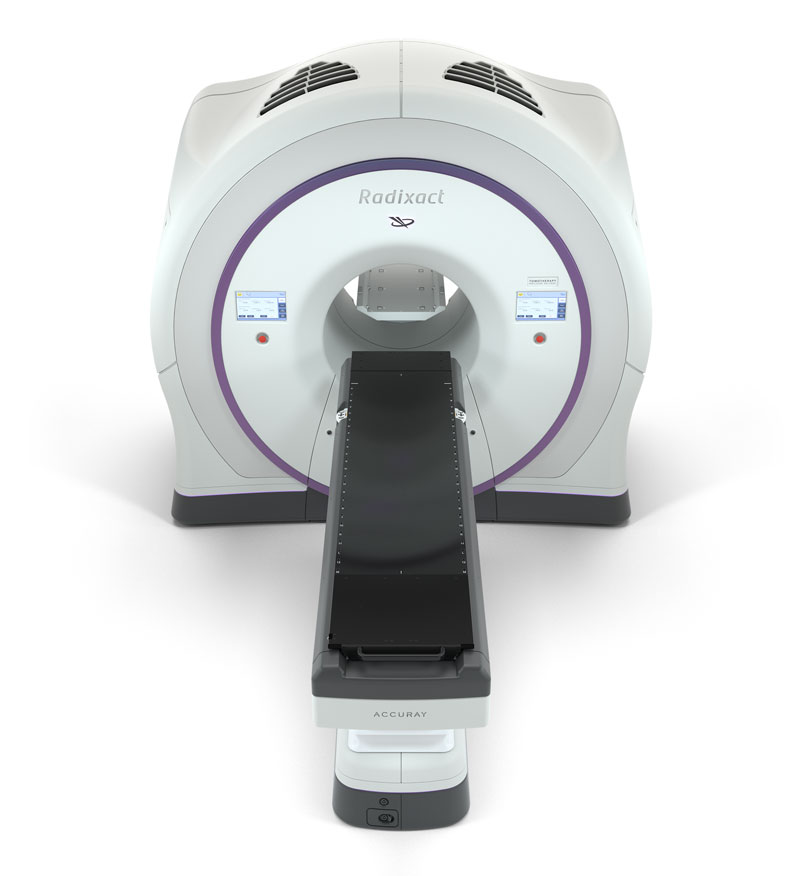

Special Techniques of Adjuvant Breast Carcinoma Radiotherapy, Breast Cancer - Radixact,

Breast Cancer - Radixact, Breast Cancer – Brachytherapy - Radiation Oncology | UCLA,